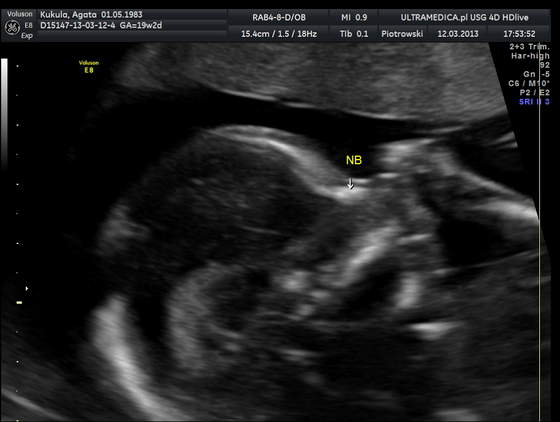

marzycielka gratuluje udanej wizyty,no ja też myślę że to dziewuszka jak nie chce się pokazać

Agata gratuluje synka!